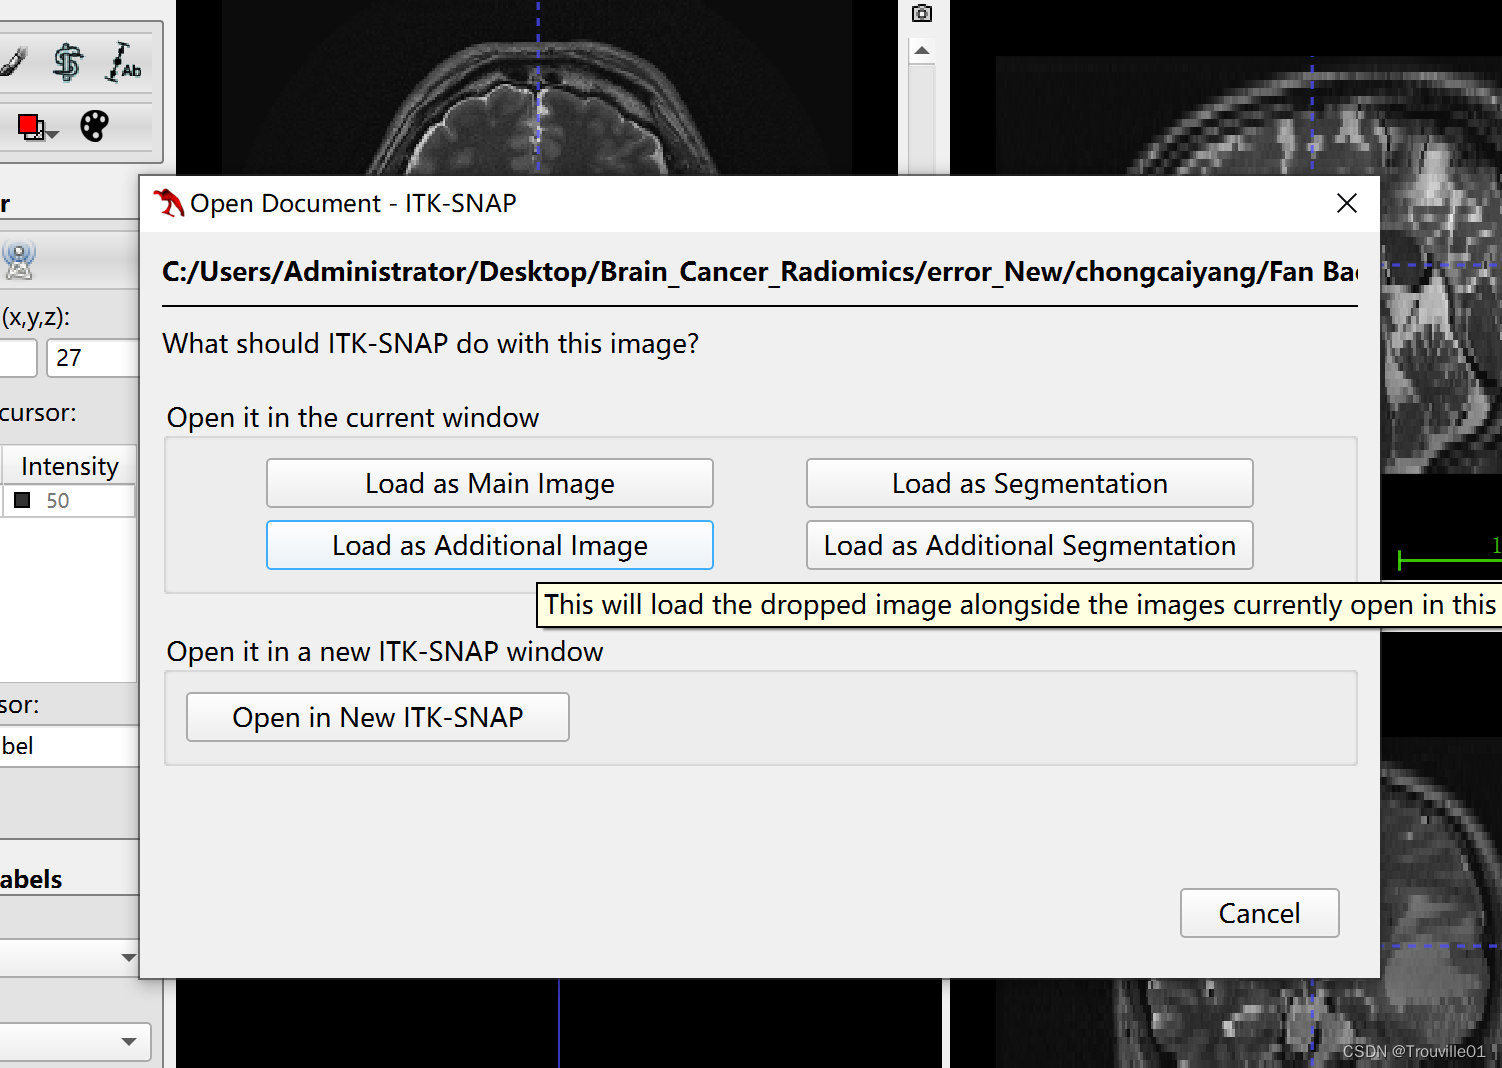

2.再拖入T1W, load as Additional image